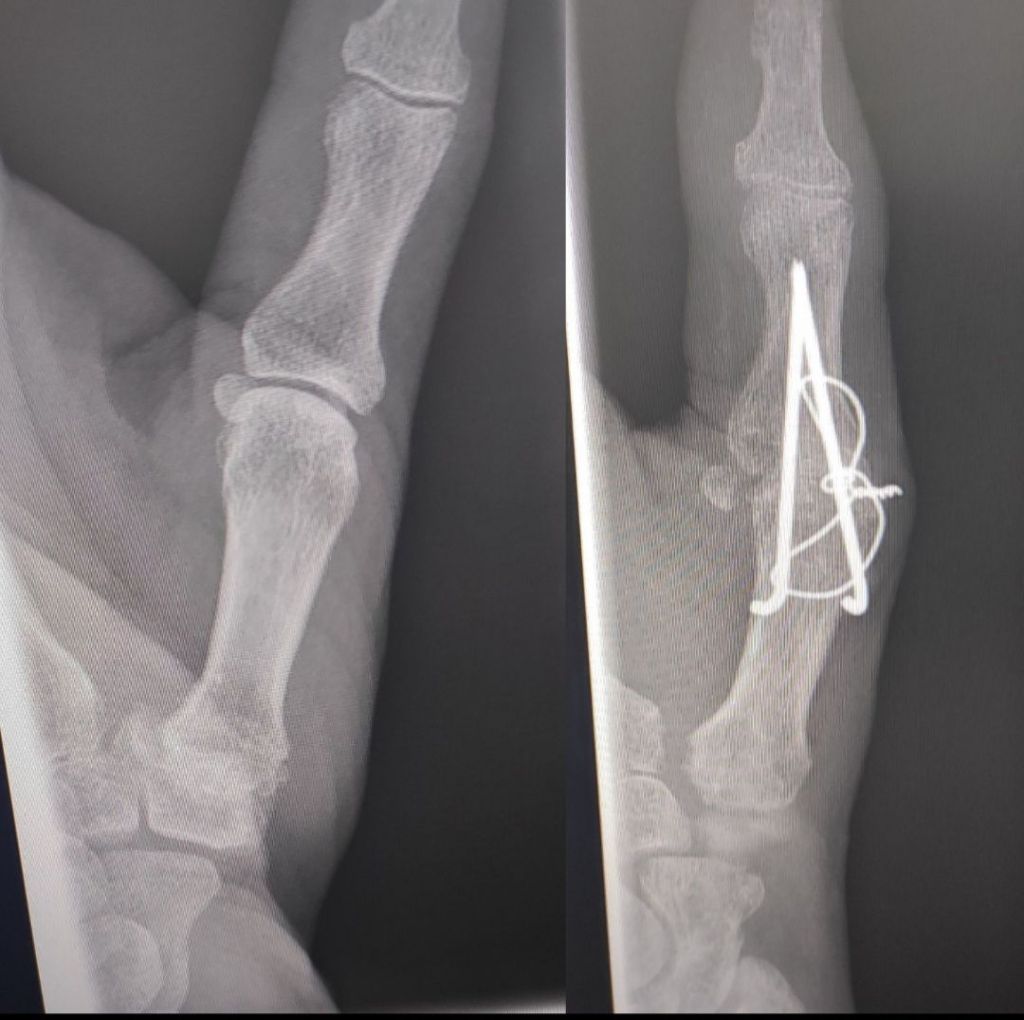

For my hand i rung up to enquire about having the tension band wire removed, as i constantly knock it. I was meant to have a follow up xray way way back in Sept, but they forgot, I got super busy over October and November, and boom it’s 2025 already. So I promised myself I would do better and I’ve booked in for 24th February.

Just the thin wire i want removing.

Where the wire is twisted together is where I catch it.

The skin over the wire is quite thin, and I fear it will poke out. And the scar tissue is building up, making the nobble bigger and bigger.